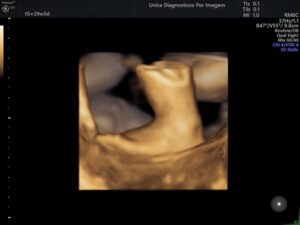

Exame importante que tem como objetivo avaliar a anatomia do feto e detectar possíveis malformações. Deve ser realizado preferencialmente realizado